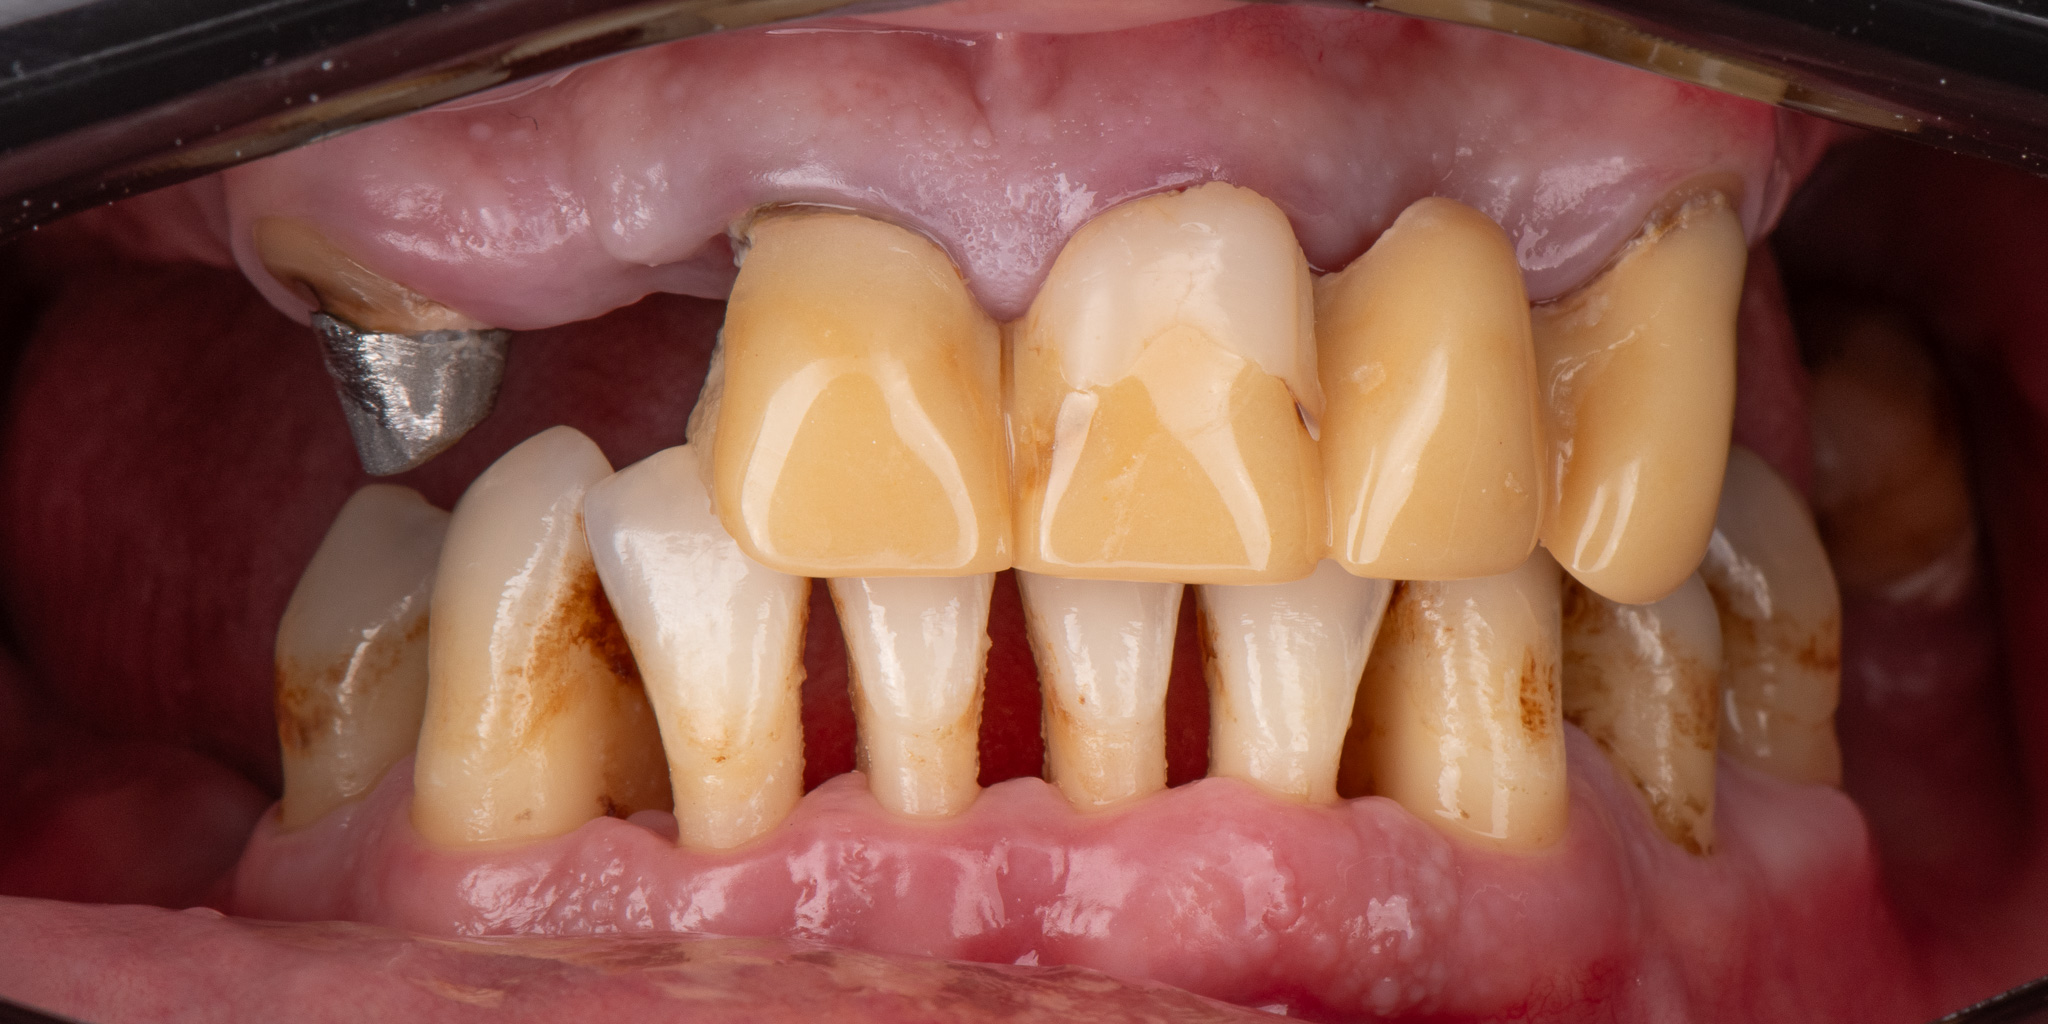

Pacjent 2

Pacjent zgłosił się w celu poprawy estetyki uzębienia, oraz wymiany użytkowanego od lat mostu protetycznego

Zaplanowane leczenie obejmowało wykonanie nowych koron pełnoceramicznych na podbudowie cyrkonowej na zęby górne oraz bezklamrowej protezy szkieletowe na zatrzaskach - rozwiązanie zapewniające wysoki komfort żucia oraz estetykę uśmiechu - brak widocznych elementów protezy na zębach własnych pacjenta.